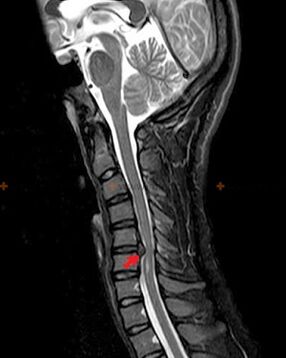

Diagnosis and radiological signs.

Osteochondrosis is an X-ray diagnosis, since a detailed clinical picture is available only at the time of exacerbation, while changes in the spine can occur with complete subjective well-being of a person.Without an X-ray examination, we can only talk about suspected osteochondrosis, because similar symptoms can be caused by other diseases (myositis, vertebral neoplasms and others).

To diagnose osteochondrosis, the following research methods are used: radiography (preferably with functional tests), MSCT and MRI.This last study is preferable because it allows us to very clearly visualize the state of the intervertebral structures.

Radiological signs of osteochondrosis include the following changes in the spine:

- Reduced height of the intervertebral discs.

- Presence of marginal bone growths.

- Violation of the location of the vertebrae relative to each other.

- Deformations of vertebral bodies and arches, etc.

The presence of the changes described above, as well as changes in the structure of the intervertebral disc, detected using MSCT and MRI, serve as reliable signs confirming the presence of osteochondrosis.